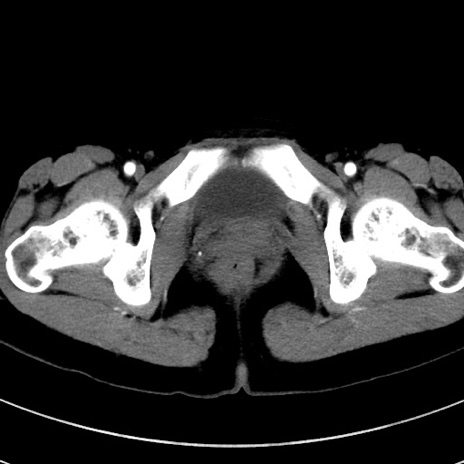

症例17(横断像)

【症例】20歳代女性

【主訴】嘔吐、下腹部痛

【現病歴】昨日夕食後に嘔吐し下腹部痛が出現。本日になっても嘔吐持続し改善しないため来院。

【身体所見】意識清明、BT 37.2℃、BP 108/67mmHg、腹部:平坦、やや硬、下腹部正中から右にかけて圧痛あり、反跳痛軽度あり、tapping pain(+)。

【データ】WBC 13600、CRP 14.94